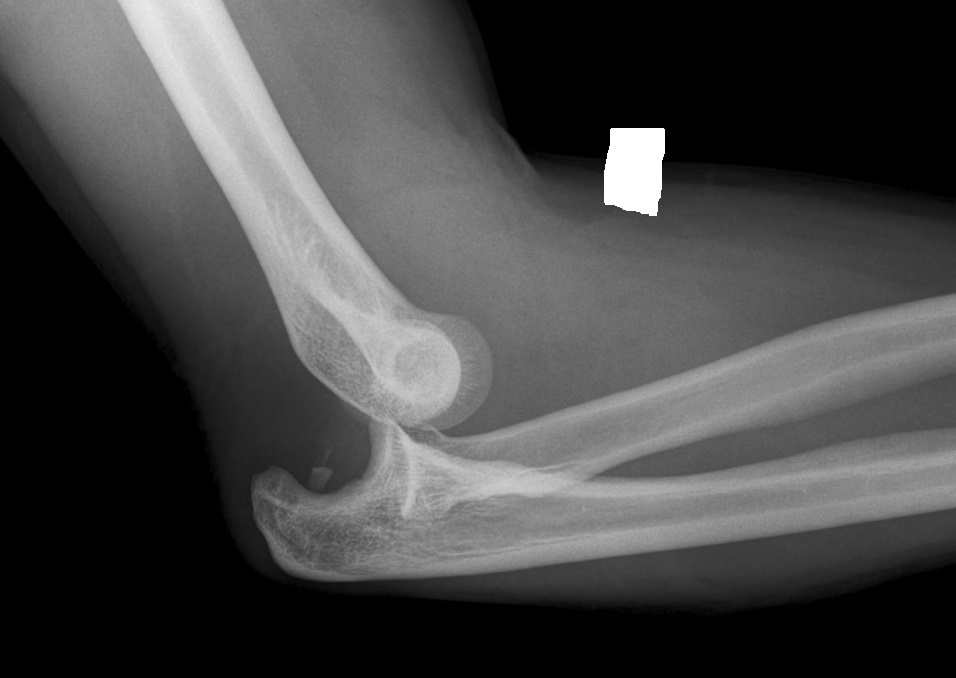

Xrays of Elbow Injuries Bone and Spine

From boneandspine.com

Xrays of Elbow Injuries Bone and Spine Elbow Dislocation Hand Swelling Patients with dislocated elbows usually experience considerable pain, obvious deformity and swelling. These symptoms may indicate nerve. Severe pain in the elbow. Elbow dislocations generally occur due to trauma and are painful and marked by swelling and obvious joint deformity. In come cases, your doctor may be able to gently move the. In some instances, a dislocated elbow. Elbow dislocation. Elbow Dislocation Hand Swelling.